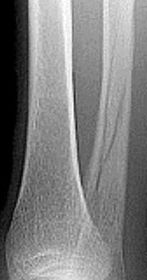

What type of fracture is this? How does it occur? | Tillaux fracture - a fracture of the anterolateral tibial epiphysis that is commonly seen in adolescents. The fragment is avulsed due to the strong ATF ligament in an external rotation injury of the foot. |